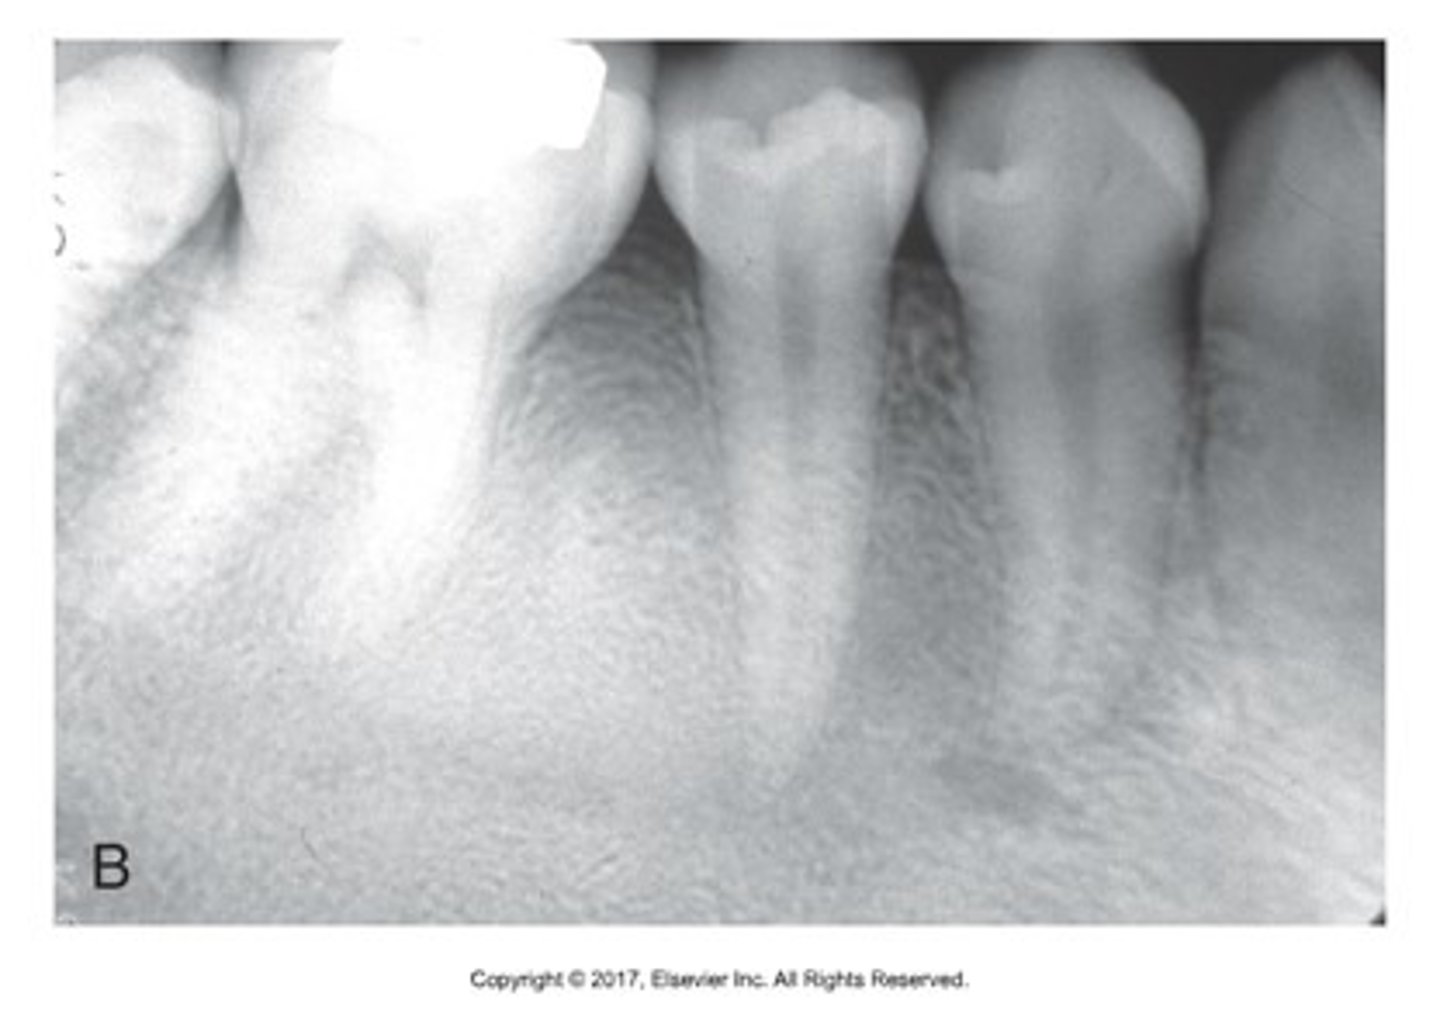

bitewing x-rays

looking at interproximal spaces to assess for caries

what is this?

what is this radiolucent area in the image?